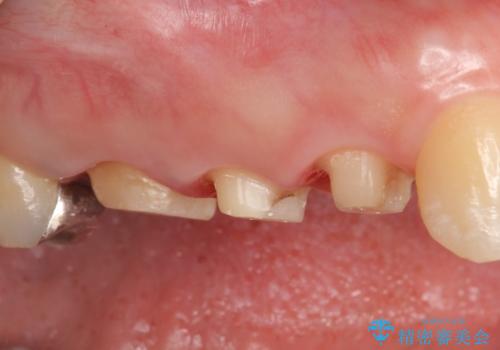

- ものを咬むと右上の歯が痛むといらっしゃった方の症例です。

検査の結果右上5の歯の神経が死んでいたため、根管治療を行った後に、オールセラミッククラウンによる補綴を行いました。

また右上6に関しては再根管治療を行い、右上4に関しては虫歯治療を行った後に、オールセラミッククラウンによる補綴を行いました。